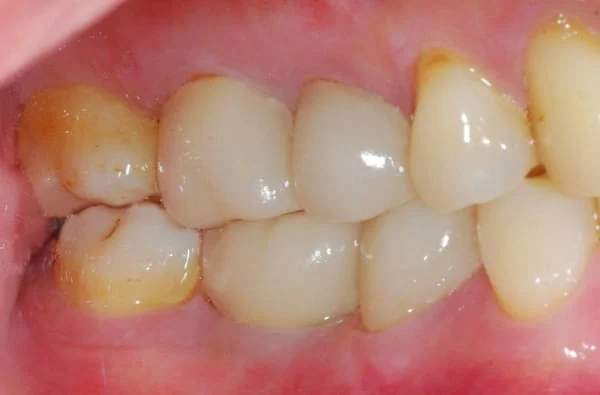

記得那天看診---醫師經由臨床上X光片仔細檢查後,發現我的這顆牙已經有牙周病的破壞,並且在牙齦下面的牙根也有蛀牙。

我同意拆掉舊有的牙套後發現 : 不只是蛀牙,而且已經蛀蝕太深,齒質已經鬆軟,無法再製作一個新的牙套。

X光片顯示已有牙周病及牙根蛀牙~汗( ̄口 ̄)!!